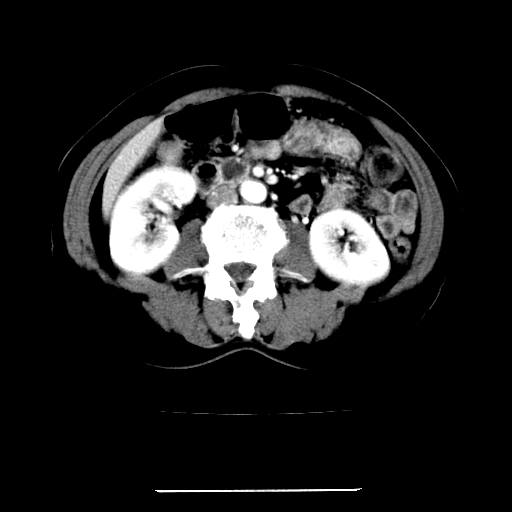

标题: CT22301:女,67岁,上腹部疼痛一周伴皮肤黄染,无发热。 [打印本页]

女,67岁,上腹部疼痛一周伴皮肤黄染,无发热。

左叶肝内胆管结石,并远端肝内胆管扩张。

考虑:肝内胆管结石继发肝内胆管扩张,右肾旋转不良。

支持肝内胆管结石并肝内胆管扩张。

肝内外胆管结石并肝内胆管扩张。

1、肝门高密度影下层面和胰头层面可见轻度胆管扩张,而静脉和延迟期均未见扫描完胰头,不能完全排除胰头占位。2、肝门部高密度影,考虑钙化或结石。

考虑肝门胆管癌伴门脉左支受侵包埋,建议mrcp进一步检查。